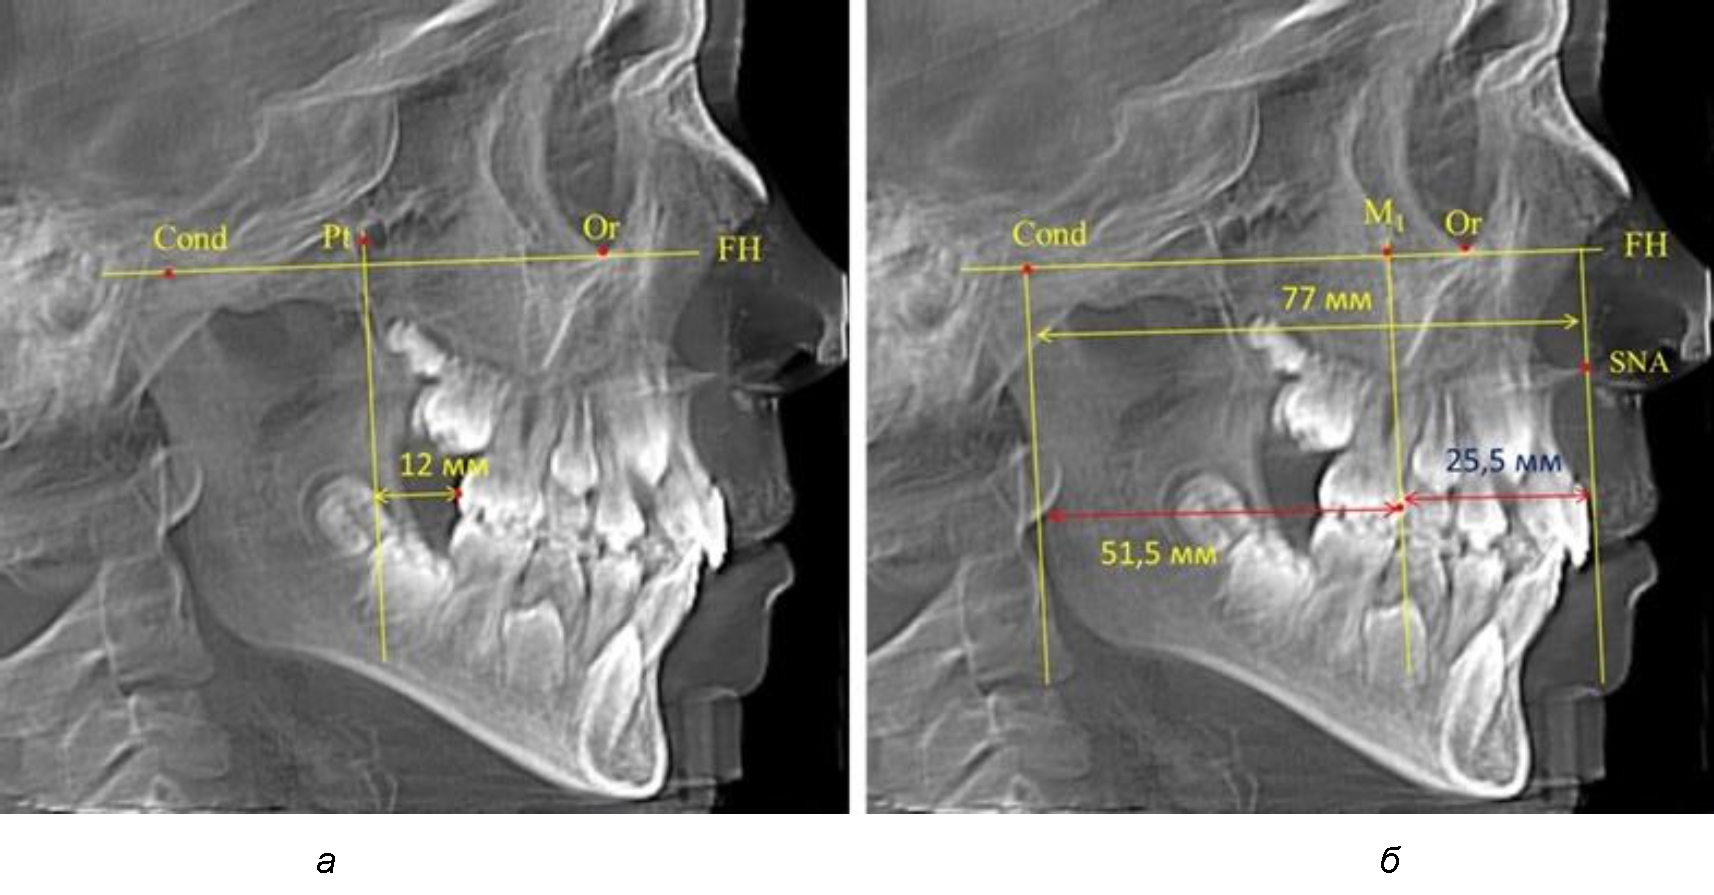

Согласно указанному методу на рентгенограммах проводили Франкфуртскую горизонталь. Учитывая мнения специалистов относительно ориентиров для построения и вариабельность положения наружного слухового прохода, в качестве задней точки использовали верхнюю выпуклость суставной головки нижней челюсти («Cond»). Передняя точка традиционно располагалась на нижнем крае глазницы и определялась как орбитальная точка Or.

Находили положение точки Pt, которая располагалась на пересечении нижнего края круглого отверстия и задней стенки крыловидно-верхнечелюстной щели, и перпендикулярно к Франкфуртской горизонтали проводили крыловидную вертикальную линию, которую принято обозначать как плоскость PTV. Расстояние от крыловидной вертикальной плоскости PTV до дистальной поверхности верхнего первого постоянного моляра определяло его положение, которое, по мнению R. E. McDonald, соответствовало возрасту пациента, увеличенному на 3 мм.

При проведении анализа к Франкфуртской горизонтали проводили передний и задний перпендикуляры. Передний спинальный перпендикуляр проходил через выступающую точку передней носовой ости (spina nasalis anterior – SNA), а задний суставной перпендикуляр опускали из кондилярной точки Cond. Молярный перпендикуляр проводили через медиальную поверхность первого постоянного моляра. Указанная вертикаль отделяла замещающие зубы постоянного прикуса от добавочных зубов (постоянных моляров), что вполне логично для анализа положения первых постоянных моляров в гнатическом комплексе (рис. 1).

Рис. 1. Метод определения положения первых верхних моляров по Ralph E. McDonald (а) и по предложенному методу (б)

Анализ проведенного исследования рентгенограмм показал существенную вариабельность практически всех линейных показателей. У молодых людей с физиологическим прикусом постоянных зубов расстояние от крыловидной вертикальной плоскости PTV до дистальной поверхности верхнего первого постоянного моляра в целом по группе составляло (18,37 ± 3,62) мм. Обращает на себя внимание большая ошибка репрезентативности из-за разницы между максимальными и минимальными значениями.

Среди анализируемых рентгенограмм минимальное значение расстояния по методу R. E. McDonald было 12 мм, а максимальное достигало 25 мм, что, по нашему мнению, обусловлено вариабельностью сагиттального размера гнатического отдела лица.